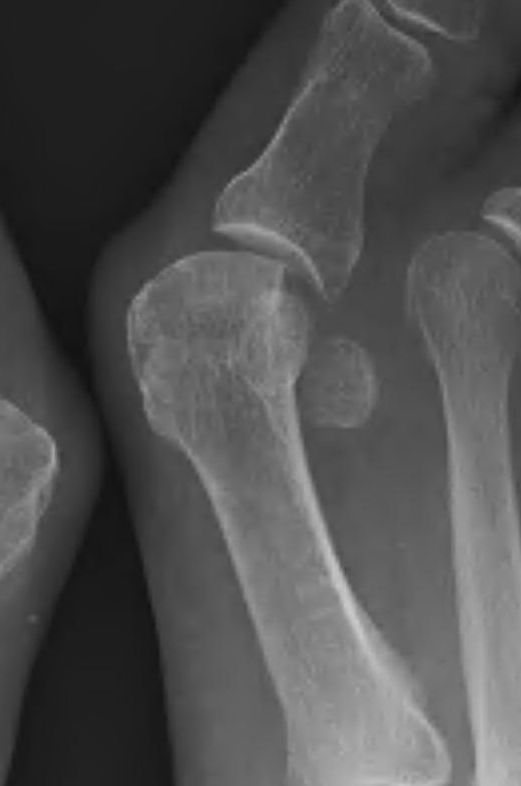

Hallux Varus

Cause

- excessive medial resection

- resection of lateral sesamoid

- excessive lateral release or medial plication

Issues

- difficulties with shoe wear

Options

- arthrodesis

- soft tissue reconstruction